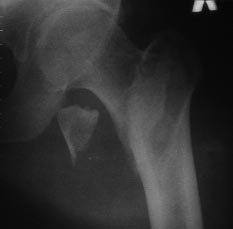

На консультацию пришел больной 44-х лет (снимки 1 и 2): упал на улице

26.11.2012г., оперирован в одном из лечебных учреждений 26.11.2012.

Сделали контрольные рентгенограммы и КТ. Хотели-бы обсудить варианты

оперативного лечения: DHS или БИОС?